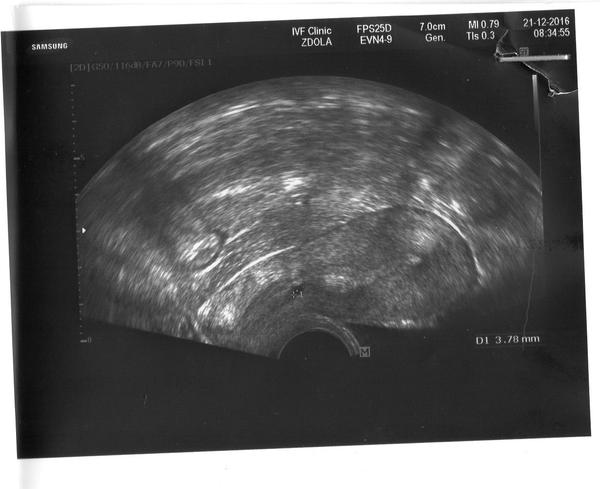

Ahoj,tak dneska jsem mela odber krve + i necakanou prohlidku.Ober krve na HCG mam 30,v pondeli jsem mela 74 takze mi to klesa.Z ultrazvuku jsem se dozvedela ze delohu mam sekrecni bez projasneni,v hrdle deloznim drobne projasneni 4mm-zlazka nebo GS.Nevim co to znamena to projasneni a ta zkratka GS.V patek mam jit na odber krve a na kontrolni ultrazvuk do nemocnice.Ze v patek v car nejsou.Fotka z delohy.